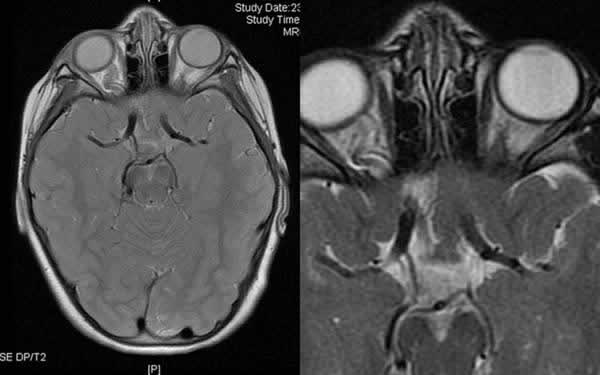

La RMN de cerebro con cortes orbitarios mostró una elongación el nervio óptico derecho y con una posible ectasia de su vaina; y el nervio izquierdo podría ser ligeramente hipoplásico (fig. 3). En su porción intracraneal dichos nervios y el quiasma presentan únicamente asimetría en la disposición sin alteraciones en el calibre o señal.

Fig. 3: RMN cerebral. Asimetría de ambos nervios ópticos, claramente mayor el derecho (posible elongación de la vaina del derecho frente a posible atrofia del izquierdo).